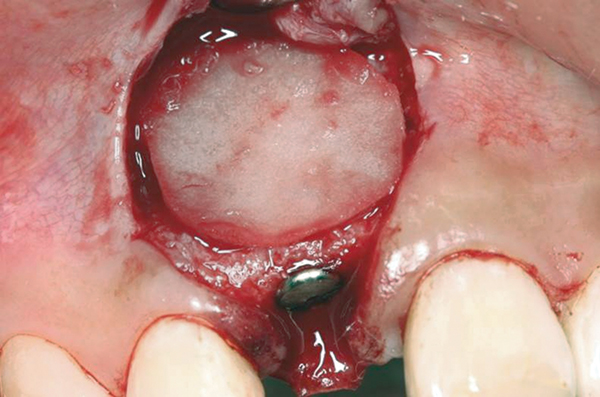

Fig 11. A horizontal releasing incision across the edentate ridge; it terminates 1 mm from the adjacent teeth.

Figure 11

Fig 14. Implant placed into the thin ridge of bone, occlusal view.

Figure 14